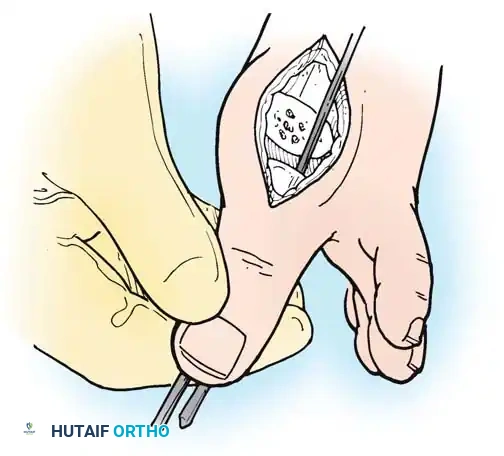

- Resection: The extensor tendons are retracted or lengthened (Z-plasty). The dorsal capsule is opened, and the collateral ligaments are sharply divided to allow plantarflexion of the metatarsal.

- Osteotomy: An oscillating saw is used to resect the metatarsal heads at the anatomical neck. It is imperative to create a smooth, parabolic cascade (the 2nd metatarsal should be the longest, tapering down to the 5th).

- Soft Tissue Balancing: The plantar plate and fat pad, which have migrated distally, are mobilized and pulled proximally under the remaining metatarsal stumps. If the toes remain contracted, closed osteoclasis or PIP joint resection arthroplasties may be performed.

- Pinning: Smooth Kirschner wires (K-wires) are driven antegrade through the toes and retrograde into the metatarsal shafts to hold the toes in neutral alignment.

Intraoperative view demonstrating the exposure and resection of the lesser metatarsal heads to decompress the forefoot and allow reduction of the dislocated digits.